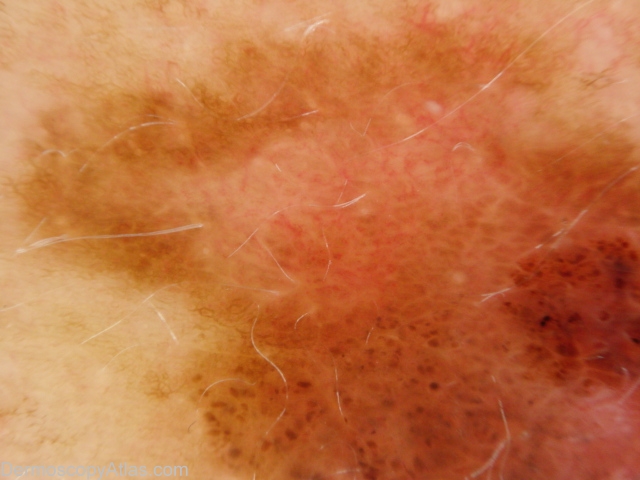

Image Number #2615 (Melanoma invasive)

Site: Abdomen

Diagnosis: Melanoma invasive

Description: Pigmented lesion on the back showing pigment dots, asymmetry of pigmentation and a negative network.

History: This lesion had developed over several months. It was brought to her attention by being itchy. It was a superficial spreading melanoma, 0.35mm thick , Clark level 2. The histopathology did show some features of regression.